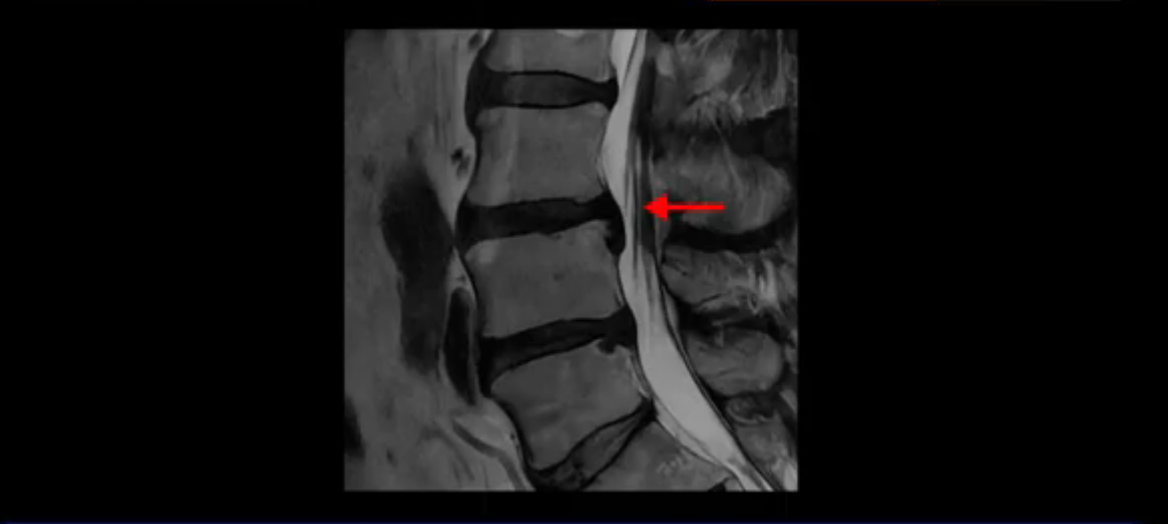

이분 MRI를 잠깐 보실까요? 보시면 두 마디가 특히 안 좋은데 3번 4번 디스크가 터져서 흘러 내려 있습니다.

보시다시피 흘러 내려온 디스크 수핵이 신경 공간의 왼쪽으로 보입니다.

그런데 이분은 4번 5번에도 디스크 파열이 있습니다.